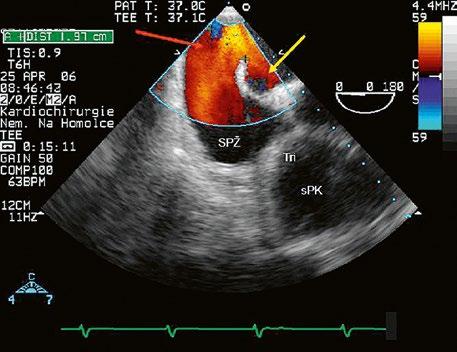

Obr. 45.17 TEE – abnormální úpony mitrální chlopně (označené šipkou) u inkompletního AVSD napříč úzkým výtokovým traktem levé komory (LVOT), přispívají k subvalvární aortální stenóze LK – levá komora, LS – levá síň